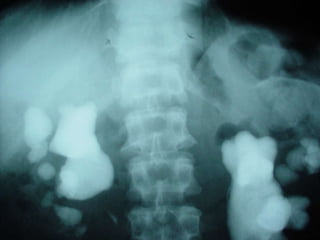

Investigations

i.v.u

19

20

21